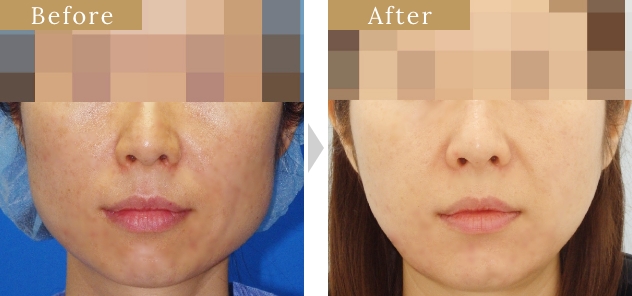

症例

症例